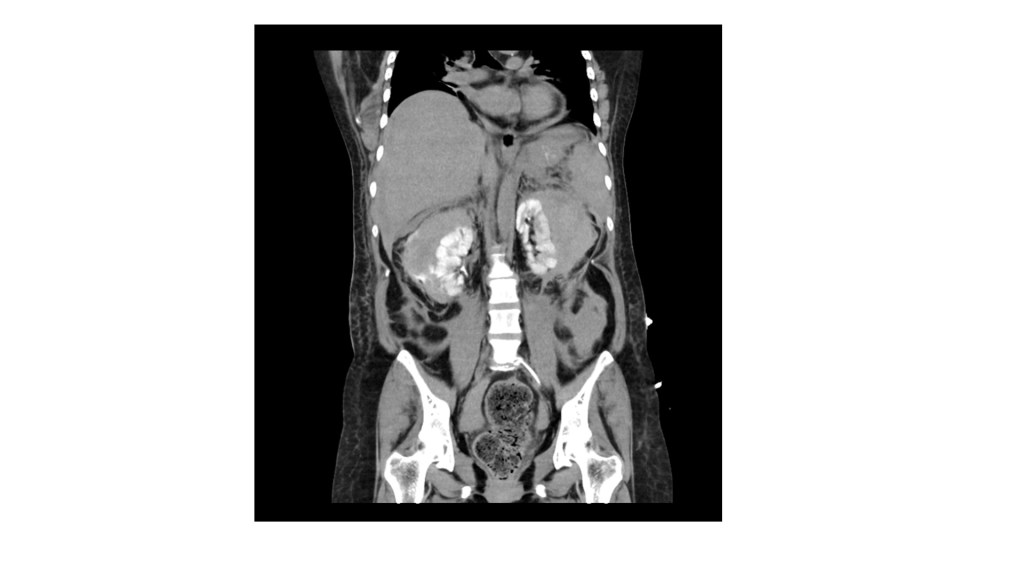

我這次報告的病患是Behçet’s disease with multiple organ involvement, 這是一個40歲女性,11年前診斷Behçet’s disease,症狀表現包含口腔潰瘍、生殖器潰瘍,眼部病變、腸胃道潰瘍、出血以及穿孔,腎臟及脾臟多個血管瘤合併血管瘤破裂出血,栓塞過2兩次、脾臟炎以及小腿脛前壞疽性膿皮症等等,幾乎可以在教科書上看到的病變都可以在這個病人身上看到,在八月時我剛好在風濕免疫科病房照顧這位病人,她在住院後又出現脾臟血管瘤破裂以及大腸出血等併發症,最後infliximab IVF後轉至腸胃科病房照顧。